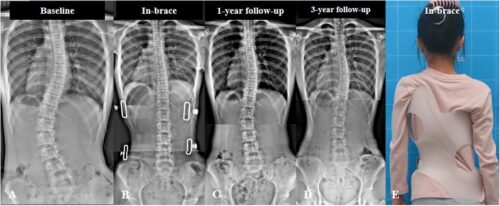

هذه التمارين تُحسن حركة المفصل وتمنع الشد العضلي الذي يؤدي إلى ميل الحوض.استخدام حزام اعوجاج العمود الفقري:

في بعض الحالات، ينصح الطبيب باستخدام أو حزام اعوجاج العمود الفقري للحفاظ على استقامة العمود الفقري أثناء فترة العلاج.

الاعوجاج حالة مستمرة ولهذا السب قد تحتاج تدخلًا في مراحل مختلفة من العمر. وبفضل وجود تقنيات التصنيف المعتمدة ، يمكن للأطباء تصميم خطة علاجية مخصصة تضمن تدخلاً جراحيًا عند الضرورة أو العلاج غير الجراحي قبل ذلك، لتفادي الاضطراب في الوظائف التنفسية أو أي أعراض متأخرة. فريقنا المحترف يضم نخبة من الأطباء والمتخصصين الذين يجمعون بين الخبرة والاحترافية لتقديم خطة علاجية غيرر جراحيه شاملة ومخصصة لحالتك، تضمن السيطرة على الانحناء ومنع زيادته.

أحدث التقنيات العالمية: نعتمد على تقنيات حديثة مثل أجهزة التقييم الدقيقة وأحزمة التقويم المتقدمة مثل PioBrace.